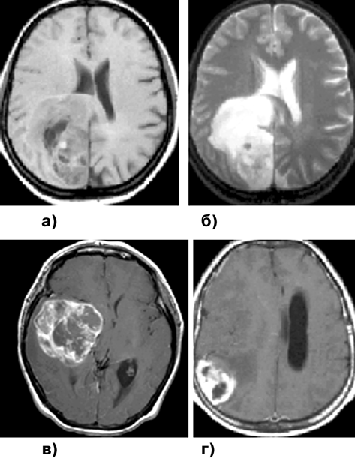

На КТ ПА обычно выглядят как округлые или овальные образования, хорошо отграниченные и имеющие гипо— или изоденсные характеристики (рис. 7а). В 10% всех ПА обнаруживаются петрификаты. Контрастное усиление носит вариабельный характер. Некоторые опухоли имеют сóлидное строение и контрастируются гомогенно, другие имеют пристеночный узел, накапливаюший контраст на фоне большой кисты. ПА, располагающиеся вблизи от 4 желудочка мозга, часто сопровождаются развитием обструктивной гидроцефалии.

На МРТ ПА выглядят как хорошо отграниченное объемное образование с макрокистами. В режиме Т1 ПА обычно имеют гипо— или изоинтенсивный сигнал, а на Т2-взвешенных изображениях опухоль чаще выглядит гиперинтенсивной. При введении препарата гадолиния отмечается интенсивное усиление сигнала от сóлидной части опухоли, в основном гетерогенного характера (рис. 7б).

Клиническая картина характеризуется длительно существующим эпилептическим синдромом. Рентгенологическая картина очень характерна: выявляется конвекситально расположенное, обычно в височной области, объемное образование, имеющее хорошо контрастируемую сóлидную часть и крупные кисты, при этом практически всегда отсутствуют признаки перитуморозного отека (рис. 7в).

Рисунок 7. Пилоидные астроцитомы:

а — ПА области подкорковых узлов справа (КТ с контрастным усилением, аксиальная проекция); б — ПА области подкорковых узлов справа (МРТ, Т1-взвешенные изображения с контрастным усилением); в — плеоморфная ксантоастроцитома теменно-затылочной области слева (МРТ, Т1-взвешенные изображения с контрастным усилением); г — олигодендроглиома заднелобно-височной области, распространяющейся на область подкорковых узлов слева (КТ с контрастным усилением)

Характерный рентгенологический признак — наличие петрификатов в опухоли, выявляемых при КТ в 90% наблюдений (рис. 7г). Ткань опухоли бывает гипо— или изо изоденсна по сравнению с окружающим мозгом. Контрастное вещество 2/3 ОДГ накапливают слабо. Редко выявляются кистозные или геморрагические изменения. Контрастное усиление, как и перитуморозный отек, характерны лишь для анапластических ОДГ.

МРТ дифференцировка эпендимом от других глиом строится в основном на их локализации, а не на различиях в интенсивности сигнала или степени контрастного усиления. Гетерогенность структуры опухоли обусловлена наличием кист (рис. 8а, б), петрификатов, опухолевой сосудистой сети. После контрастного усиления отмечается средней интенсивности негомогенное усиление. Дифференциальный диагноз эпендимомы бокового желудочка необходимо проводить с субэпендимомами, нейроцитомами и астроцитомами.

Рисунок 8. Эпендимома и субэпендимома:

а+б — эпендимома, расположенная пери— и интра-вентрикулярно в области переднего рога правого бокового желудочка (МРТ с контрастным усилением); а — Т1-взвешенные изображения, б — Т2-взвешенные изображения

Макроскопически опухоль имеет вид плотного узла, исходящего из стенки желудочка и расположенного в его просвете. Для субэпендимом характерны богатая васкуляризация и обилие микрокист (рис. 8в, г). Субэпендимомы прогностически благоприятны. Опухоли боковых желудочков в большинстве случаев могут быть удалены тотально. Тотальное удаление опухолей, исходящих из дна IV желудочка часто невозможно, однако темп роста этих опухолей крайне низок, в связи с чем безрецидивный период может быть достаточно продолжительным.